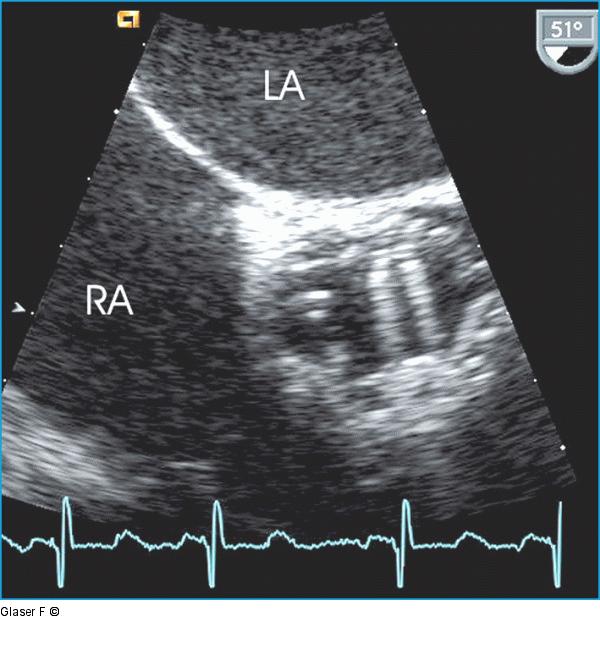

Abbildung 8: Transösophageales Echo - Aortenklappe Transösophageales Echo der Aortenklappenprothese (Querschnitt 51°): Das Klappenspiel ist besser, aber immer noch nicht optimal beurteilbar. |

Transösophageales Echo der Aortenklappenprothese (Querschnitt 51°): Das Klappenspiel ist besser, aber immer noch nicht optimal beurteilbar. |